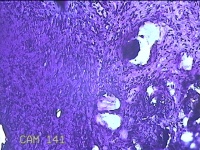

性别

女

年龄

43岁

临床诊断

异常子宫出血

一般病史

月经不规则2年余,发现宫颈赘生物近1年,活检外口可见多个赘生物。

标本名称

宫颈内容物

大体所见

灰白粉红色不规则碎组织1.2x0.8x0.3cm一堆。

图3